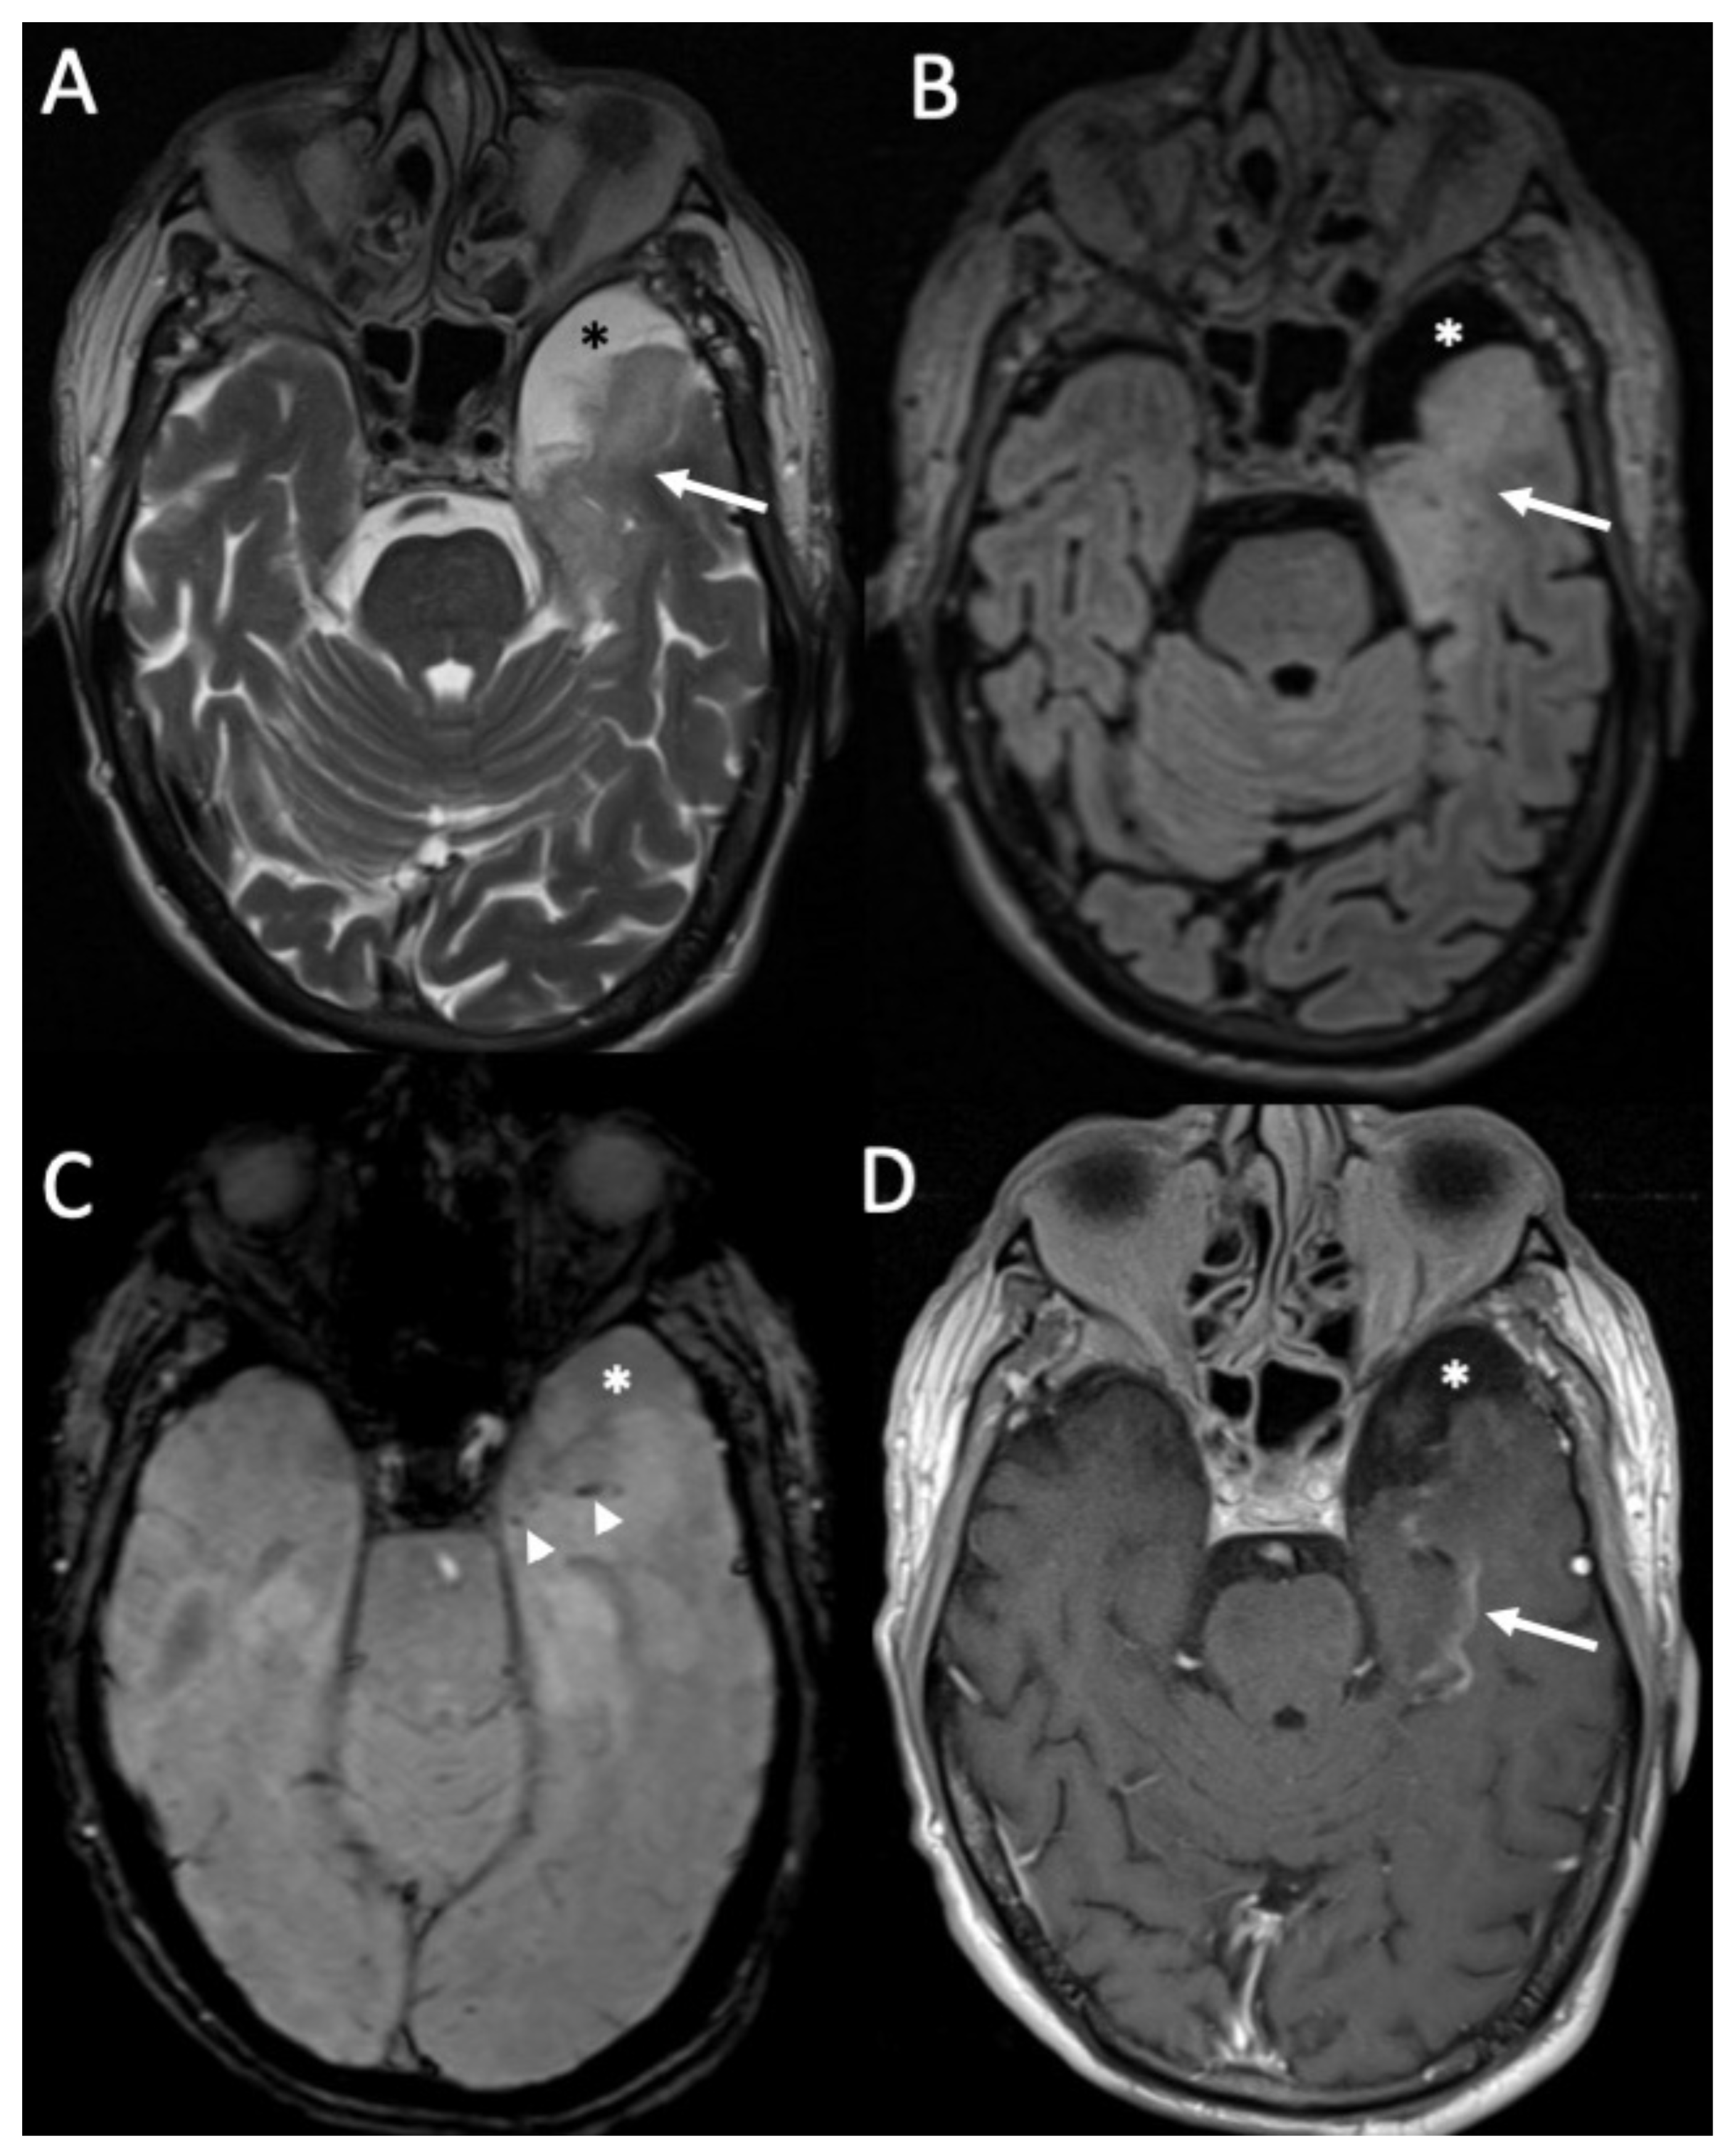

Figure 1.

Axial FLAIR (A), T1 (B), coronal (C), and sagittal FLAIR (D) show diffuse hyperintensity on FLAIR and T1 of the subarachnoid spaces mainly in the cerebral convexity (arrows in A,B) in a patient with Streptococcus Pneumoniae meningitis. Note also concomitant cerebellitis, which appears as diffuse cortical hyperintensity on FLAIR of the cerebellum (arrowheads in C,D), with herniation of the cerebellar tonsils (arrow in D).